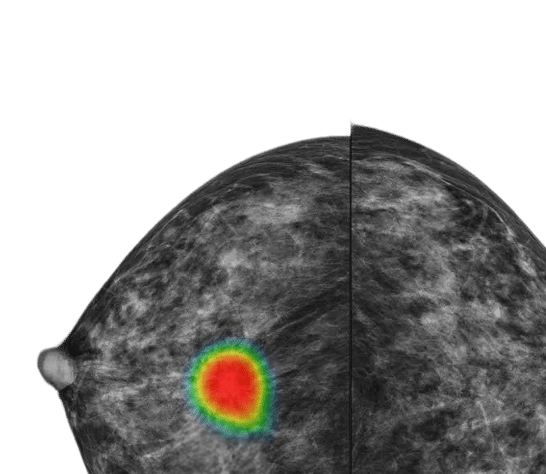

Lunit INSIGHT DBT (3D) AI-powered mammography software enhances lesion detection in digital breast tomosynthesis exams, helping radiologists interpret complex cases with greater precision.

Each suspicious lesion is assigned an abnormality score (0–100), helping quantify malignancy likelihood. Location is clearly marked using heatmaps or contours, and lesion types—such as masses (including architectural distortion and asymmetry), and calcifications—are identified for targeted interpretation. The best slice for lesion visualization is marked on the navigation bar for quick review.